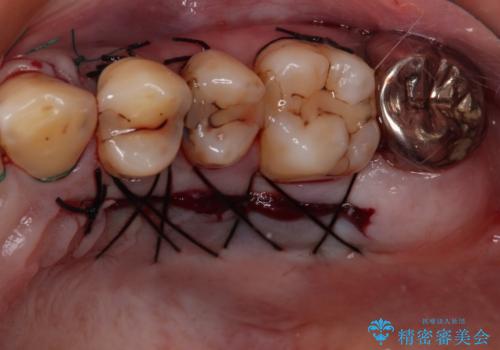

犬歯を中心に、露出量の多かった歯は十分に被覆することができました。

また、歯根のシルエットが見えた術前の状態と比較して、術後は歯肉が非常に厚くなっている状態となりました。